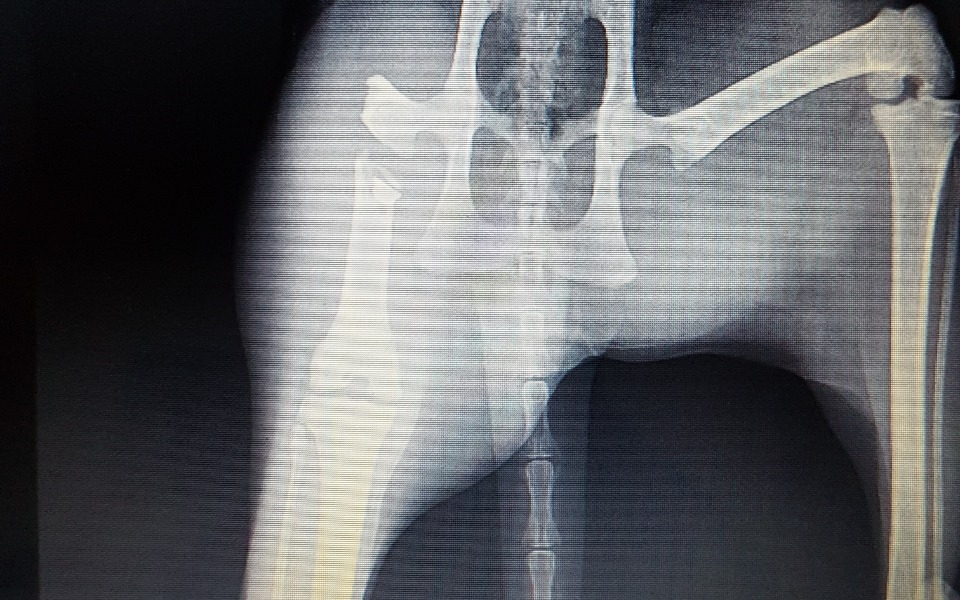

przyszla w nocy 6 maja do domu i juz wtedy miala problem z chodzeniem (kulala). zastanawialismy sie co sie dzieje, zaczekalismy jeden dzien przed pojsciem do weterynarza (w nadzieji ze moze jej przejdzie). 8maja udalam sie z kicia do weterynarza. na miejscu dostalam wiadomosc, ze noga jest zlamana i potrzebne jest rtg. po zrobieniu przeswietlenia wszystko bylo jasne - zlamanie przez postrzelenie wiatrowka. kosc zlamana w udzie. potrzebna jest operacja, ale koszt jest bardzo wysoki, mianowicie (z antybiotykami) moze wyjsc nawet kolo 4 tysiecy zlotych. apeluje o pomoc w sfinansowaniu tej operacji, bedziemy bardzo wdzieczni. shisha, choc jest tylko kotem, wiele dla nas znaczy, traktujemy ja jak czlonka rodziny.